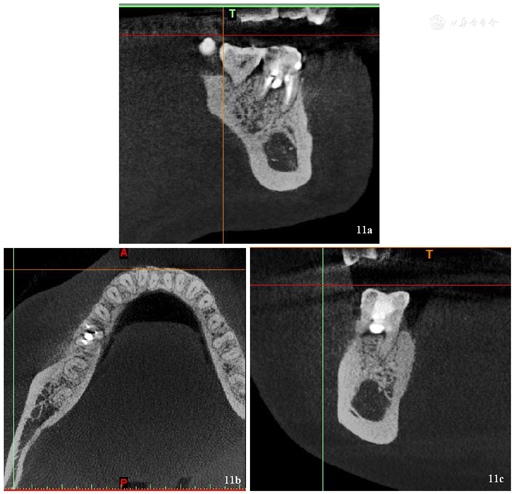

术后3个月复诊(2021年8月31日),患者自述高嵌体修复治疗后患牙未见明显异常,咬合正常,无松动。检查: 46高嵌体完好无破损,边缘密合,无松动,叩诊(-),咬诊(-),无咬合高点,牙龈颜色正常(图10),行局部小视野CT示:根尖周组织暗影明显缩小,远中根管穿孔区及近中根管壁穿孔区暗影较上次复诊X线片对比骨密度明显增高,暗影减轻,牙周膜间隙较上次恢复,余未见明显异常(图11、图12)。继续随访中。